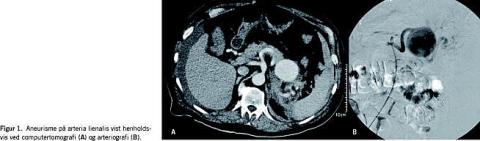

Under den seneste indlæggelse blev AMI afkræftet og en bed side-ekkokardiografi viste normal pumpefunktion. Patientens blodtryk faldt i løbet af de næste par døgn til 59/35 mmHg, og han var på et tidspunkt pulsløs i 30 s, men fik spontan sinusrytme igen. Der blev i løbet af to dage observeret et fald i hæmoglobin fra 7,9 mmol/l til 4,9 mmol/l, og blodtransfusioner blev påbegyndt. Smerterne persisterede, hvorfor der blev udført CT, der viste et 5,6 cm stort aneurisme på arteria lienalis og tillige blødning omkring aneurismet, pancreas og leveren (Figur 1A). Ved gennemgang af CT fra to år tidligere kunne man se samme aneurisme, der da målte 4 cm i diameter.

Patienten blev efter CT'en overflyttet til Odense Universitetshospital mhp. behandling. Da der var mistanke om ruptur valgte man at foretage endovaskulær embolisering af a. lienalis. Igennem sheath i a. femoralis blev et emboliseringskateter ved hjælp af røntgenkontrast og gennemlysning fremført via aorta og truncus coeliacus til a. lienalis (Figur 1B). Med spidsen af kateteret beliggende i aneurismesækken blev der udløst coils, og disse flød med blodstrømmen til afgangsarterien og emboliserede denne. Herefter blev kateteret retraheret, og tilgangsarterien blev ligeledes emboliseret med coils. På den måde blev aneurismet totalt ekskluderet. Efter indgrebet var patienten velbefindende og kunne tilbageflyttes til stamsygehuset den følgende dag.